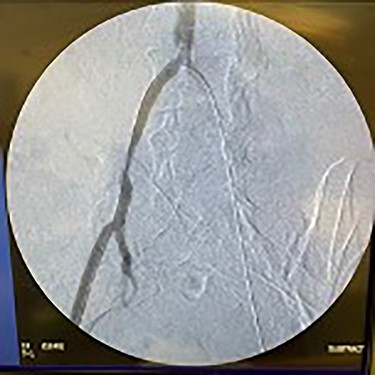

Catheter arteriogram results showed significant occlusion of the left iliac artery (Figs 3 and 4), the right iliac artery (Fig. 1), as well as the distal abdominal aorta (Fig. 2). There were numerous collateral vessels noted, indicating the presence of long-standing proximal stenosis (Fig. 1). The decision was made to use angioplasty to help widen the areas of stenosis. An 8 mm × 40 mm Passeo balloon was advanced from the right femoral artery into the left iliac artery (Fig. 7) and insufflated to 6 mmHg (Fig. 6). The balloon was allowed to remain expanded for 1 min and then was deflated. Next, the distal aorta was repaired in a similar fashion. The balloon was advanced into the distal aorta from the right femoral access and insufflated to 12 mmHg (Fig. 8). The balloon was allowed to remain expanded for 90 s.

Fluoroscopy of bilateral iliac arteries showing significant arterial disease.